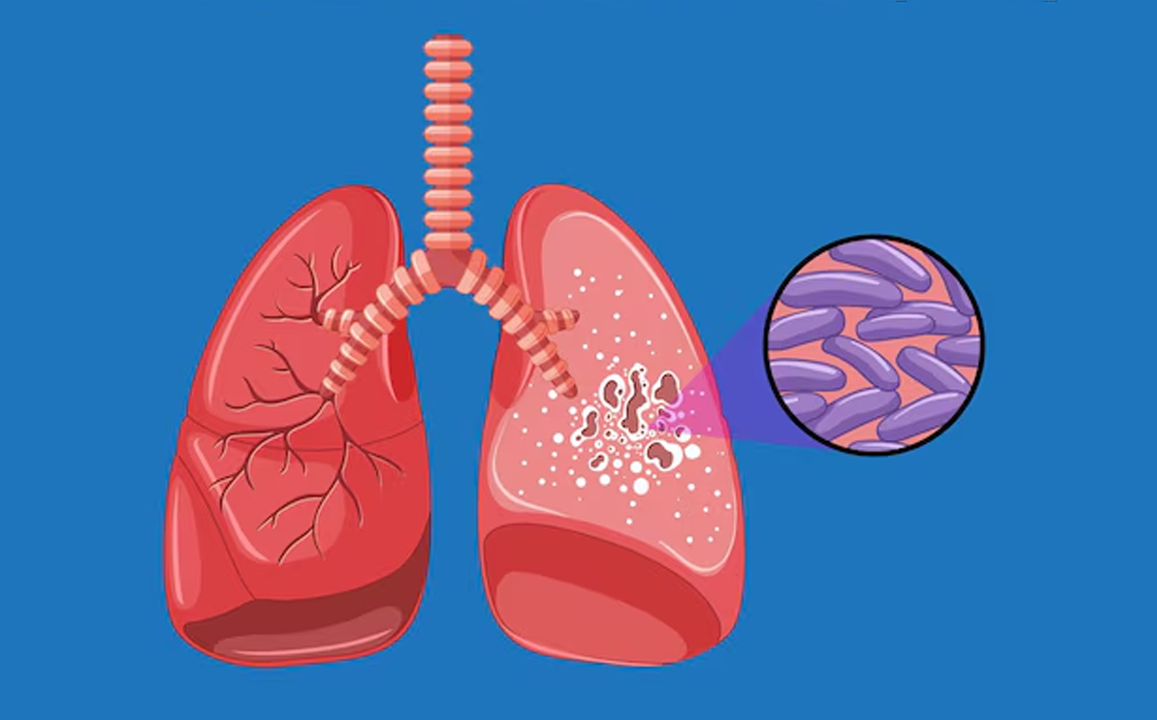

Tuberculosis

Tuberculosis is a contagious bacterial infection, primarily affecting the lungs, causing coughing, fever, weight loss, and fatigue.